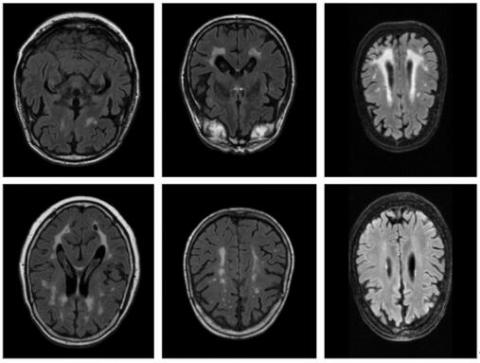

Figure 3. Sample images from the WMH segmentation challenge dataset

In 2017, the WMH Segmentation Challenge event was held within the scope of MICCAI 2017 in order to compare the performances of existing methods for the automatic segmentation of WMH of presumed vascular origin and to reveal new segmentation approaches. WMH Segmentation Challenge dataset was created for the event and made available to the participants [59, 60].

In the dataset, there are images obtained from 3 different hospitals and 5 different MR scanners. In the dataset, 3D T1-w and 2D FLAIR image sequences were acquired for each patient. Ground truth masks were created on FLAIR images through manual marking by the expert.

In this study, a total of 60 MR sequences from the WMH Challenge dataset were used in experimental studies. From a total of 735 images, 572 (78%) were used for training, 119 (6%) were used for validation and 44 (6%) were used for testing. Sample images from the WMH Segmentation Challenge dataset are given in Figure 3.